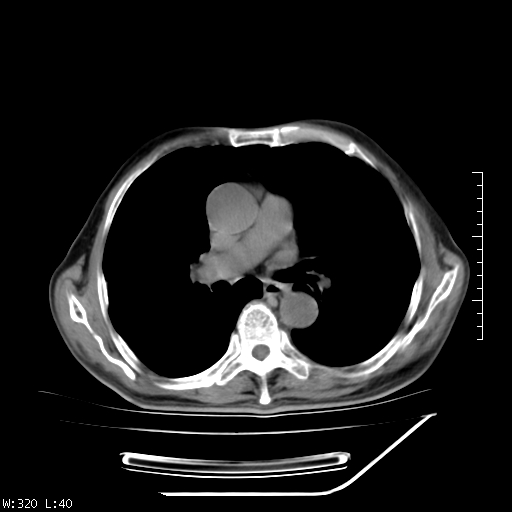

标题: CT23994:男、72、咳嗽、气短两月余,近来消瘦。 [打印本页]

标题: CT23994:男、72、咳嗽、气短两月余,近来消瘦。

右上肺实变,与胸膜关系密切,右肺容积缩小,隆突下淋巴结增大,考虑1 肺结核 2 肺癌

右上肺大片状密度增高影,与胸膜关系密切,内见低密度透亮影,胸膜下可见三角形不张影,左下肺沿支气管走形结节影,纵膈内淋巴结显示。考虑结核并疤痕性不张可能性大,建议穿刺活检,排除肺泡癌。